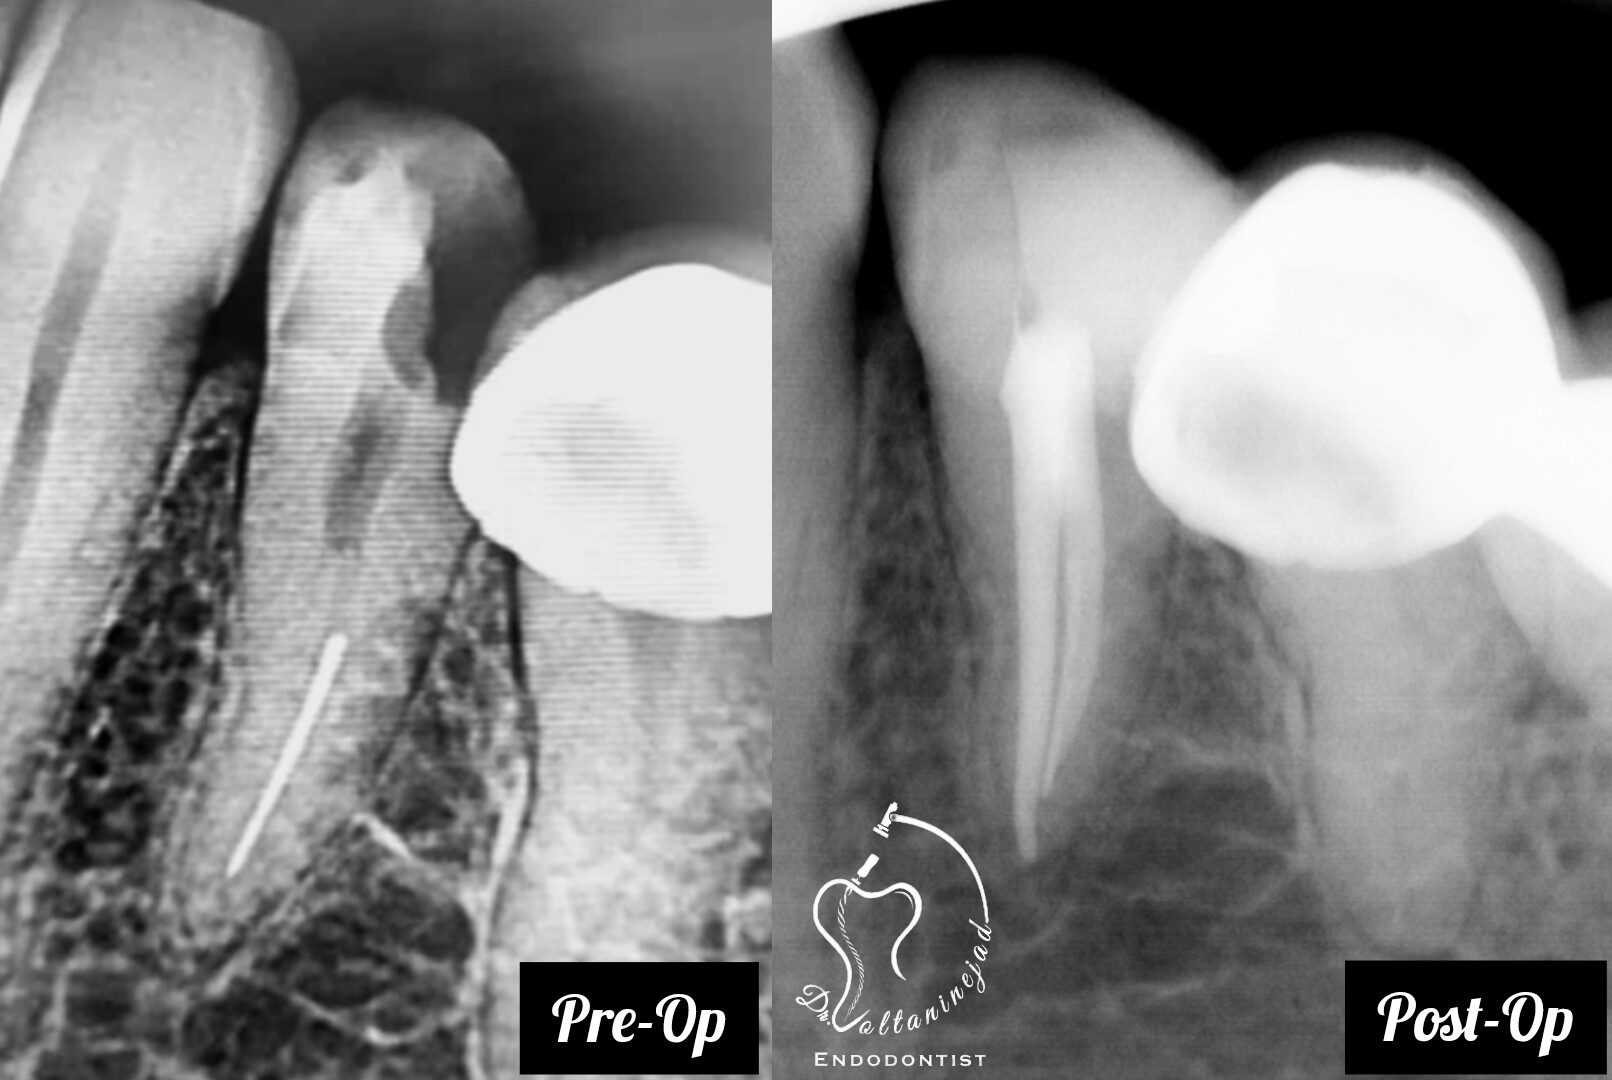

🔹 خارج کردن فایل شکسته از کانال

• شرح کوتاه: بیمار با درمان ریشه نامناسب و فایل شکسته در کانال مراجعه کرد. فایل با میکروسکوپ خارج شد و درمان ریشه مجدد انجام شد.

• نتیجه: رفع درد و حفظ دندان بدون نیاز به جراحی.

خارج کردن فایل شکسته